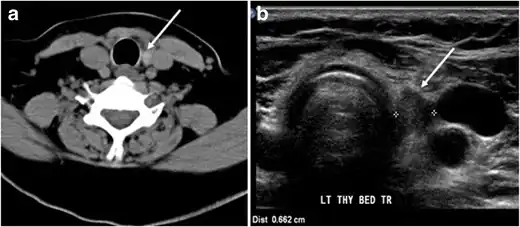

Fig. 18. Lingular thyroid in a 33-year-old male who presented with oropharyngeal bleeding. an Axial enhanced neck CT scan at the level of mandible demonstrates a 3 × 3 × 3.4 cm round, partly well-delineated, heterogeneously enhancing lesion (white arrow). It is predominantly on the left side of the oropharynx and to some extent at the mid part of the base of the tongue. The thyroid gland was normal (not shown). b Image of the anterior face and neck taken 20 minutes after Tc99m-Pertechnetate injection shows absent thyroid radiotracer uptake in normal thyroid anatomical location (black short arrows). There is an area of increased uptake (long black arrows) corresponding to the posterior tongue mass identified on CT scan.[1]